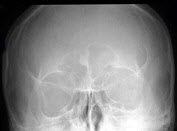

290、单项选择题

男,32岁,头晕、头痛多年,额窦X线检查如图所示,最可能的诊断是()

A.右侧额窦骨瘤

B.右侧额窦囊肿

C.右侧额窦骨岛

D.正常额窦

E.右侧额窦软骨瘤